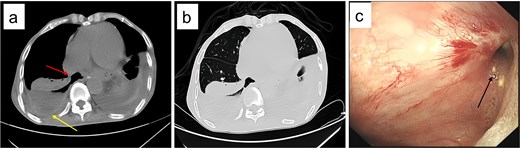

Upon admission, chest computed tomography (CT) and gastroscopy confirmed persistent esophagopleural fistula and empyema (Fig. 1a-c). A multidisciplinary team formulated a stepwise management plan: Stage 1: Under CT guidance, a chest drainage tube was reinserted. The nutrition team optimized nutritional status, correcting hypoalbuminemia and anemia. Thoracic drainage fluid culture revealed multidrug-resistant Pseudomonas aeruginosa; based on antimicrobial committee advice, local treatment (twice-daily 250-ml saline irrigation) was prioritized over systemic antibiotics. Stage 2: After 1 month, the drainage fluid became clearly transparent. However, CT showed unchanged fistula and cavity (Fig. 2a). Thus, a surgical plan was developed. CT-based three-dimensional reconstruction (Fig. 2b-d) guided surgery. Under general anesthesia, a 15-cm incision was made over the 10th rib. The latissimus dorsi muscle flap was dissected with preserved blood supply (Fig. 3a). Intercostal structures were preserved. The 9th and 10th ribs were transected 2 cm from the purulent cavity margin; the 11th and 12th ribs, 2 cm from the vertebral column. After thorough irrigation, a washable drainage tube was placed with its distal end toward the fistula. Muscle flaps were inserted into the cavity and sutured with antibacterial Vicryl (Fig. 3b and c). Finally, the incision was sutured (Fig. 3d). Stage 3: Skin depressions were compressed with cotton pads and a chest strap for 2 weeks (Fig. 4a). Sensitive antibiotics were administered for 2 weeks; intermittent saline irrigation-maintained drainage patency. The drain was removed at 3 weeks. Postoperative CT showed satisfactory recovery (Fig. 4b and c); the duodenal tube was removed 1 month later, and the patient resumed a normal diet gradually. As of July 2025, he remained symptom-free with no recurrence.

Post-admission chest CT and gastroscopy. (a) Mediastinal window showing esophageal fistula (arrow) and empyema (arrow); (b) lung window confirming the 67 × 36 × 117 mm right empyema; (c) gastroscopy identifying a 8 mm fistula (arrow) 38 cm from incisors.